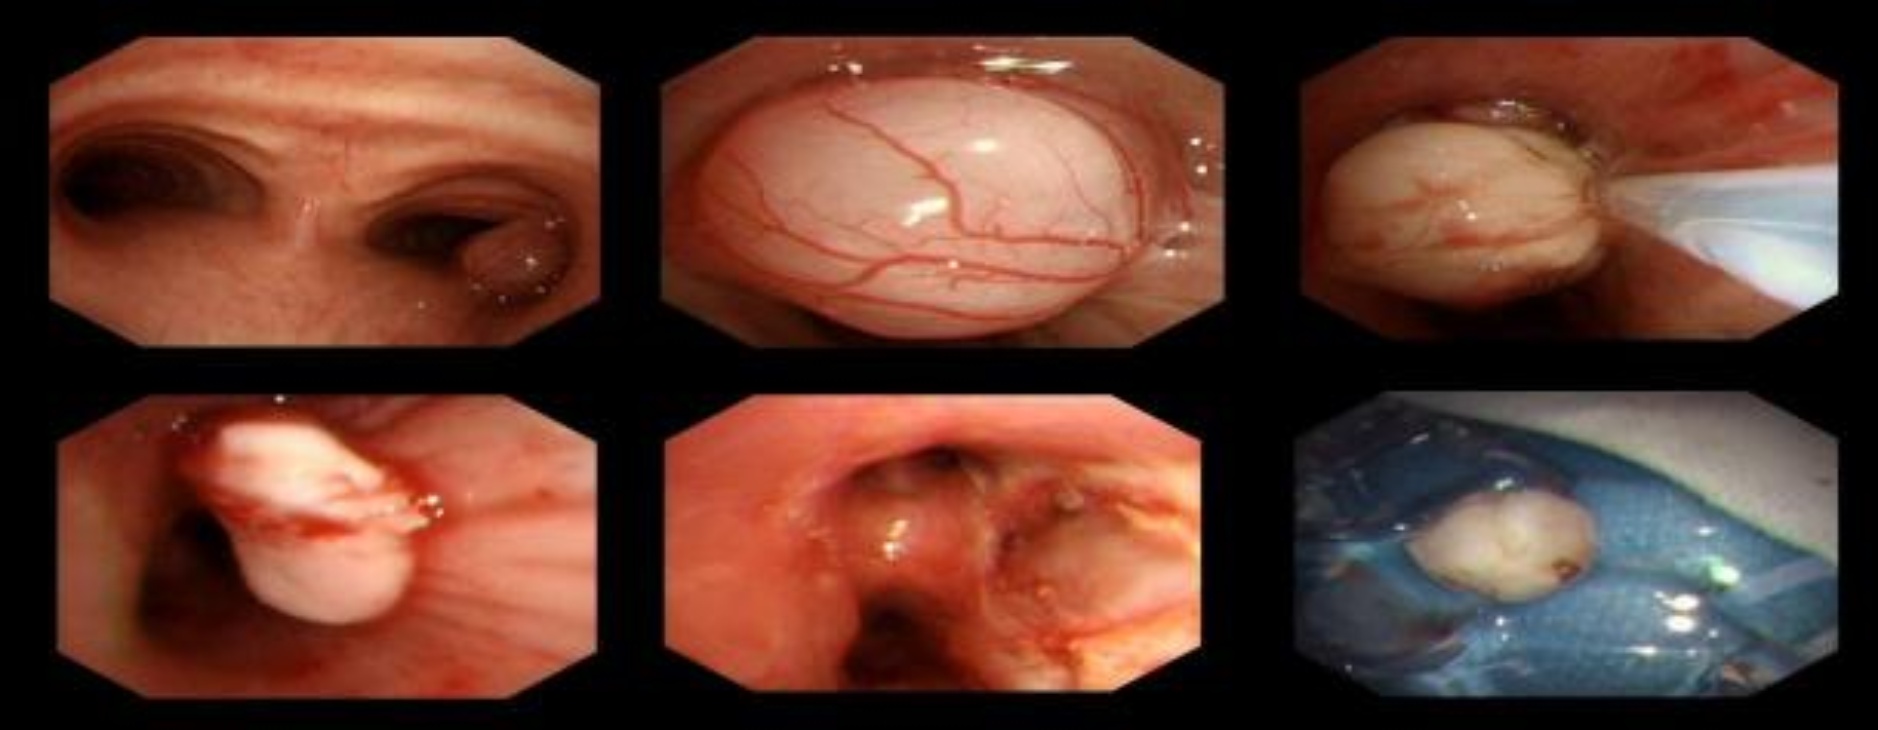

入院后2025年2月7日行胸部CT增强扫描检查提示:胸廓对称,纵隔气管居中。双肺纹理增多,右主支气管内见结节状高密度灶,边缘清楚,直径约1.1 cm,增强扫描两期CT值分别为31 Hu、63 Hu,强化程度不均匀;余段及段以上支气管通畅;双肺见少许索条影。双肺见多个直径小于5 mm实性小结节影。双肺门不大。纵隔内未见明显增大淋巴结。双侧胸腔未见积液。双侧胸膜未见增厚(见图1)。于2025年2月7日在全麻下行电子支气管镜检查示右主远端近上叶开口处可见一新生物堵塞管腔(见图2)。新生物予以径向超声探查,未见明显血管征象,予以电圈套器套取新生物,予以电切切除,右主远端支气管通畅。结束退镜;过程顺利,患者无不良反应;检查结束后患者心率70次/分,血氧饱和度98%,血压110/70 mmhg安返复苏室。常规病理活检肉眼见:右主支气管内新生物:灰白色组织1块,大小约1.5 × 1.3 × 0.6 cm,切面灰白色,质稍韧。病理诊断:(右主支气管内新生物)平滑肌瘤(见图3)。免疫组化结果:瘤细胞示SMA (+),Desmin (+),CD34 (−),HMB45 (−),H-Caldesmon (+),CD117 (−),Melan A (−),Ki67 (+)约1%。结合形态学特点和免疫组化检查,病理诊断为原发性支气管平滑肌瘤。于2025年2月9日好转出院。术后3月对患者进行电话随访,诉当地医院复查胸部CT未见肿瘤复发,一般状况良好。

Figure 2. Fiberoptic bronchoscopy identified a neoplastic lesion obstructing the lumen adjacent to the orifice of the upper lobe at the distal end of the right main bronchus. Radial ultrasound evaluation of the lesion revealed no significant vascular signals. The lesion was subsequently captured with an electrocautery snare and resected via electrocautery. Gross examination of the routine pathological biopsy specimen demonstrated a grayish-white tissue mass within the right main bronchus, measuring approximately 1.5 × 1.3 × 0.6 cm, with a grayish-white cut surface and a slightly firm consistency

2. 纤维支气管镜检查发现右主支气管远端上叶开口附近管腔内有一新生物堵塞。病灶径向超声评估未探及明显血管信号。随后使用电凝圈套器抓取病灶并予电凝切除。常规病理活检标本肉眼观察可见右主支气管内灰白色组织肿块,大小约1.5 × 1.3 × 0.6厘米,切面呈灰白色,质地稍韧